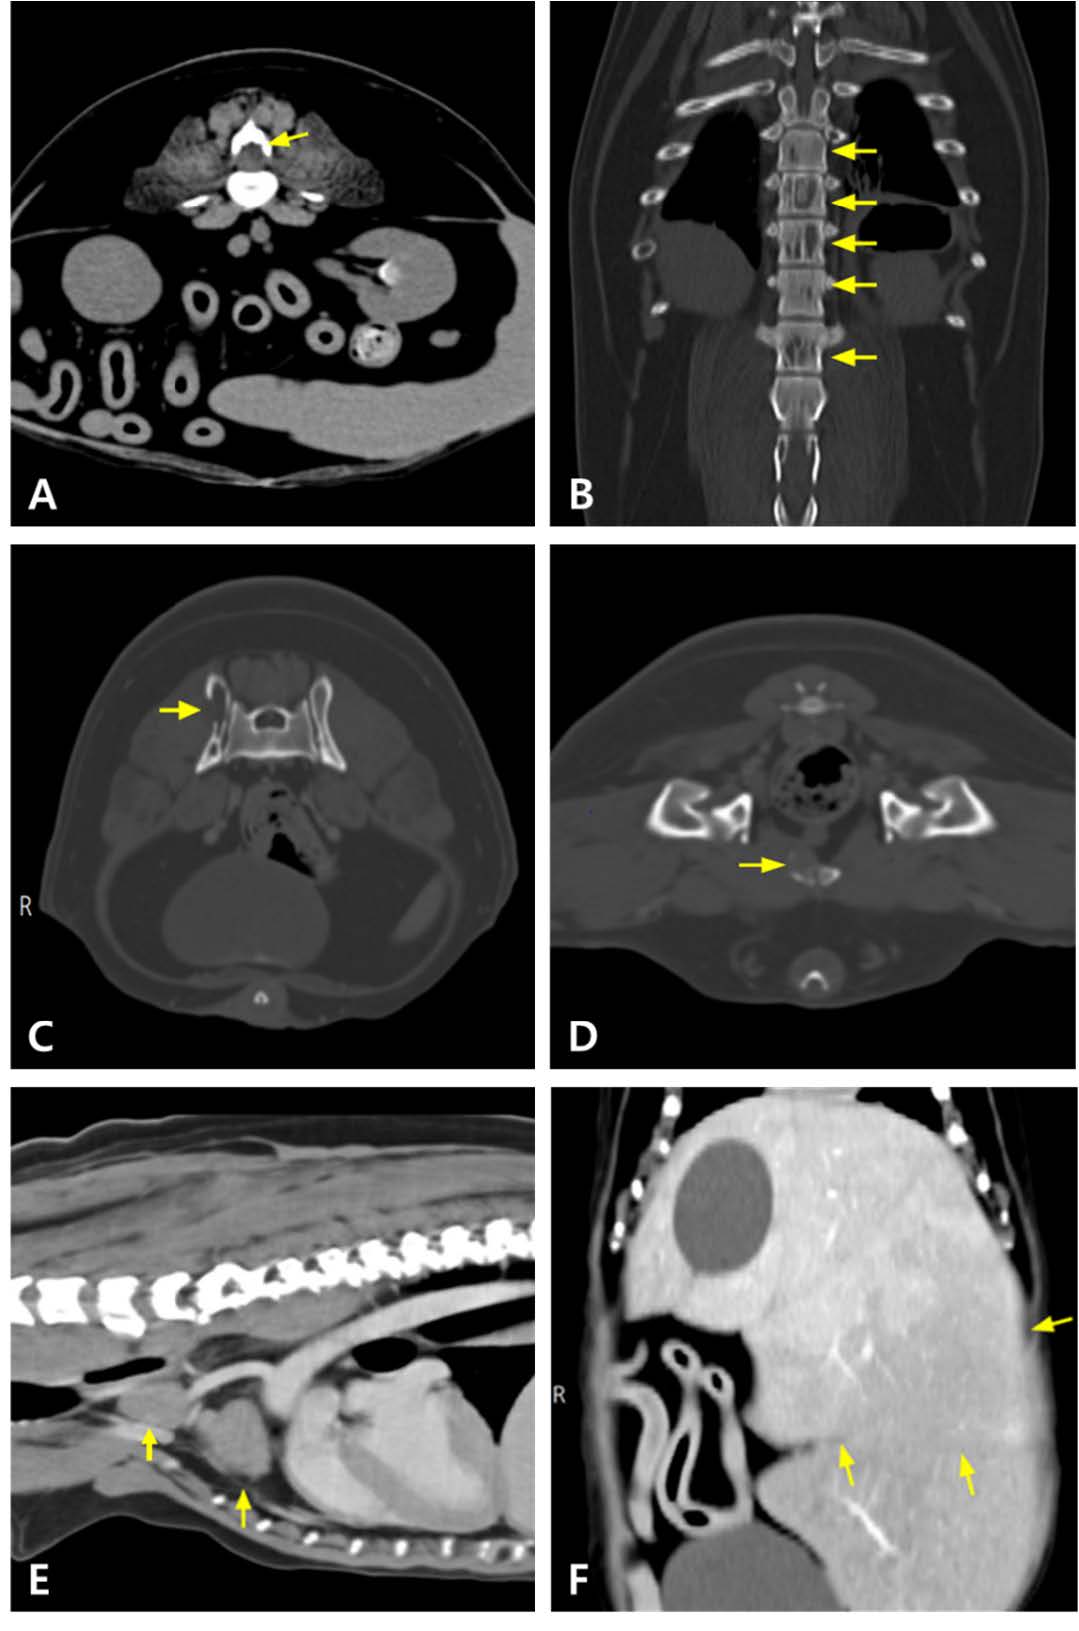

因双侧后肢共济失调就诊于当地动物医院。最初症状类似于跛行,怀疑是关节疾病。给予非甾体抗炎药治疗3周,但症状逐渐加重。随后进行了CT和MRI。影像学检查发现第三腰椎椎体处有一肿块,压迫L3-L4水平脊髓。在多个椎体(包括髂骨、耻骨和肋骨)中也检测到肿块。还观察到纵隔和腹部淋巴结肿大,肝脏肿大且存在低密度肝病变,肝脏、脾脏、右肾上腺和肾脏实质变化,这些表现引发了对多发性骨髓瘤的怀疑(下图)。随后该犬被转诊接受化疗。

↑ MRI结果。在T2加权、未增强的矢状面图像上,L3-L4水平的肿块(箭头)正在压迫脊髓。